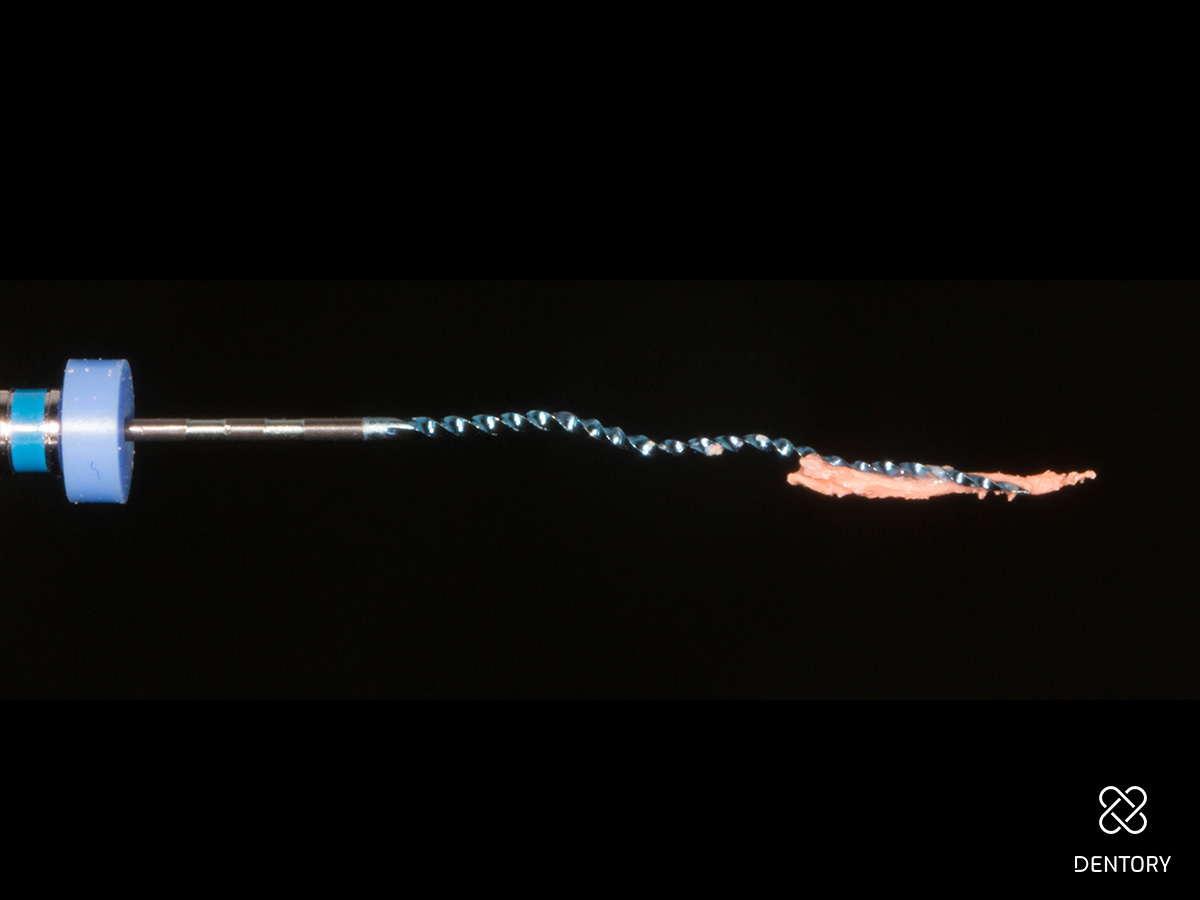

Abbildung 6

Initiale Entfernung der alten WF mit 2500 rpm. Dabei entsteht oft dieses Bild, bei dem die alte Guttapercha am Instrument hängen bleibt. Während der Revision wurde mit NaOCl gespült, welches zuvor mit einem milden Chelator gemischt wurde. Danach erfolgte eine elektrische Längenmessung mit einer Handfeile. Der Zahn wurde temporär mit Komposit verschlossen - eine medikamentöse Einlage erfolgte mit 2%-Chlorhexidin-Gel.